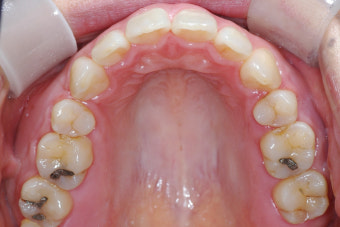

- 임플란트는 일반 치아보다 음식물이 끼기 쉬움 → 치실·워터픽 등 적극 활용.

- 자연 치아 vs 임플란트: 자연 치아는 완충 역할을 하는 치주 인대가 있으나, 임플란트는 없어 합병증 발생 위험↑.

- 합병증(나사 풀림, 파절 등)은 초기 자각 어려움 → 정기 검진 필수.

- 조기 검진은 작은 문제도 빠르게 발견 → 큰 문제 예방 가능.